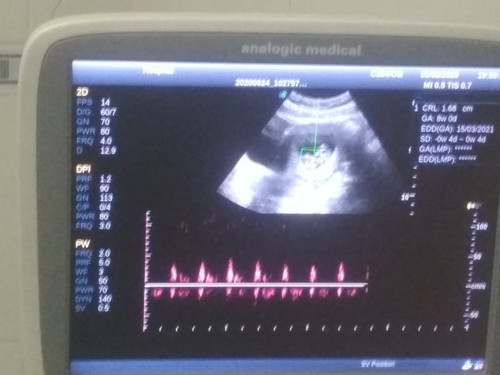

Menurut Bunda Akurat mana Usia kehamilan berdasarkan HPHT dengan Usia kehamilan berdasarkan USG? Jadi aku tadi USG usia hamil aku di USG 8w 0d, sedangkan kan kalau HPHT itu 10w 2d. Baru kusadari setelah pulang USG. Pas di dokternya gak kutanyakan karena si dokter sudah bilang bayi kecil kalo usia 10w dan gak gerak. Auto panik duluan sampe gak sempet nanya apa2. Btw sebelum hamil siklus haid aku gak normal bun... ada yang mau sharing atau memberikan info yang bunda tau mengenai ini?

Aku pas pertama usg dulu juga gitu bun.. hasil usg 8w0d hpht 9w1d... tapi kata dokter gpp,detak jantungnya bagus... disuruh balik sebulan lagi,Alhamdulilah pas balik sesuai hpht soalnya aku rajin minum sumil...